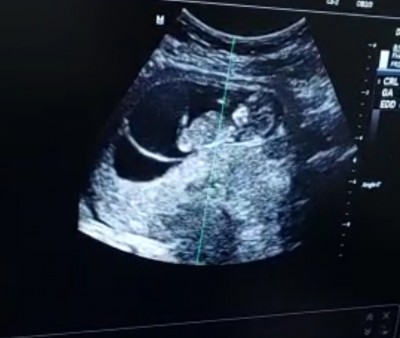

Kızlar size zahmet sipalarima bir tahmin yapar mısınız Allah isteyen herkese hayırlı sağlıklı evlatlar nasip etsin inşallah şimdiden teşekkür ederim

bu da diğeri canlar

Kac haftalik canim Allah baguslasin saglikla kucakla benim icime erkek degdu

12 haftalık  çok teşekkür ederim yorumunuz için inşallah cümlemiz sağlıkla alalım kucaklarımiza inşallah canım ❤️

Alttaki erkek gibi üsteki anlamadım cnm ama oda erkek sanırım çift yumurta ikiizimi

Evet canım çift yumurta inşallah bir kız bir erkek olur ya çok istiyorum  Allah razı olsun yorumunuz için teşekkür ederim hayırlısı sağlıklısı olsun inşallah artık ❤️

Çift yumurta ikizi galiba. Benim de ikiz kızlarım var. Rabbim ak yüzle kurtarsın

Ustteki erkek alttaki zaten kız  <3 saglikla gelsin bebislerin